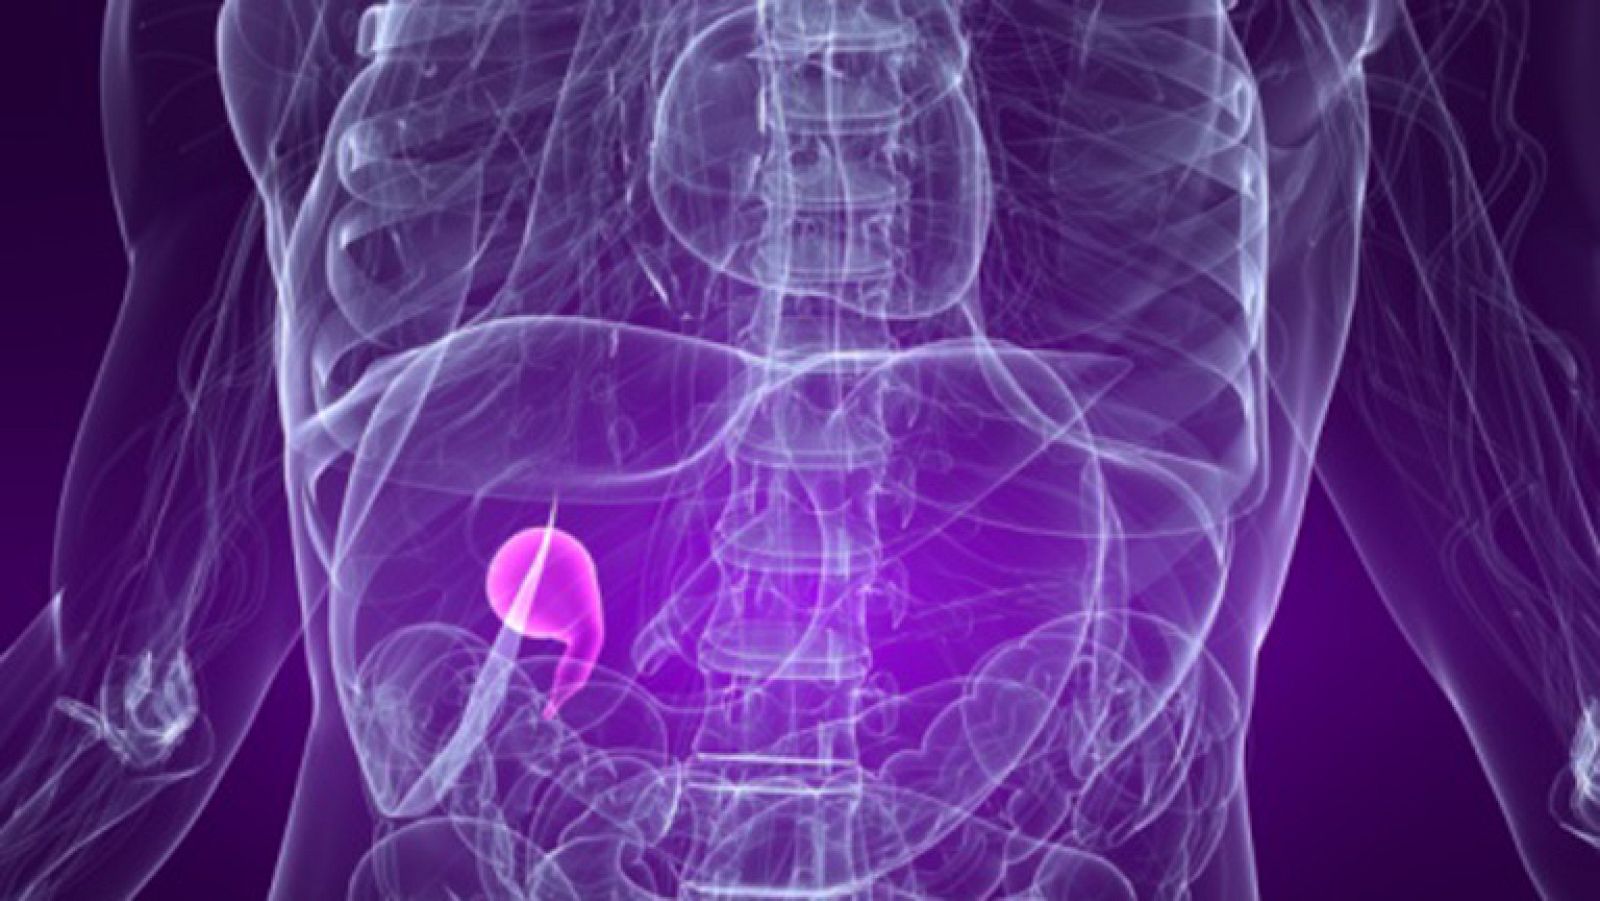

Problemas de vesícula

¿Por qué es malo el sobrepeso? ¿Tiene relación con el colesterol alto? Hablamos de cómo prevenir las "piedras" y las digestiones pesadas. Histórico...